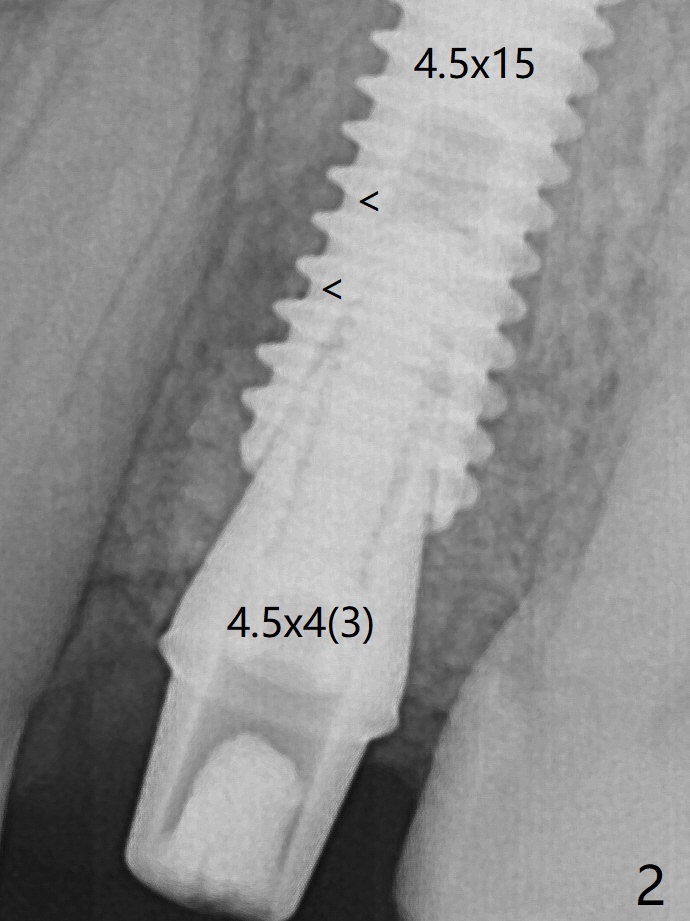

Due to short apical bone (Fig.5,7), a long dummy implant (3.8x15 mm) is placed with periimplant space immediately post extraction (Fig.1 *). The final implant is larger (4.5x15 mm) with simultaneous periimplant bone graft (Fig.2 <,当时骨粉一定用的多,压得紧,好像进入螺纹). The native bone (higher in bone density, Fig.9 white arrowheads, as compared to black one (for bone graft)) appears to have grown into the space between implant threads 5.5 months postop. Sinus Lift Last Next XinWei, DDS, PhD, MS 1st edition 06/21/2019, last revisionn 06/13/2021